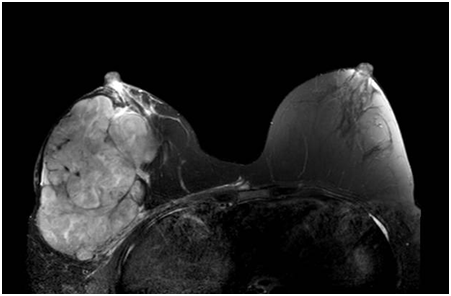

据了解,刘女士是在一年前开始发现右侧乳房有一个黄豆大小的肿物,当时未予引起重视,直到几个月前,感觉瘤子一下子变大了,并且一天比一天大,才匆匆忙忙来医院检查。刘女士穿着宽松的上衣,右手托着右胸,缓缓走进病房,边走边喘着气。掀开上衣,眼前的一幕惊呆了查体的管床医生,整个右乳被肿瘤占据,测量约有20cm,皮肤发红,足足比左侧乳房大了一倍。眼前的这个巨大的肿瘤,不仅仅影响到刘女士的工作生活,最重要的是,还不明确性质。

张敏敏副主任当即与科室负责人莫军扬主任医师以及科室成员协商进一步的诊疗方案,根据经验,这个未知的炸弹倾向于叶状肿瘤或者乳腺癌,结合患者的B超、钼靶及磁共振检查,先给刘女士做右乳肿物的穿刺,及皮肤活检,病理回报为良性的叶状肿瘤,红肿的皮肤也未见癌成分,但由于穿刺取材有限,具体的结果需要完整的标本来确诊。病理结果让刘女士看到了希望,在严密的计划之后决定手术切除这个重如泰山的“石头”。手术的难度在于瘤体太大,剥离需要十分仔细且耐心。

完善好术前准备之后,张敏敏副主任带领年轻医生们加班加点,历时3小时,在凌晨之前顺利完成了这场“卸弹仪式”。术中发现胸大肌及肋骨已经被压迫得轻微变形。术后乳腺甲状腺外科一病区医护团队细心照料,刘女士顺利出院,幸运的是,术后的病理结果也是良性的叶状肿瘤。出院前拉着医生的手不住道谢:“张医生,真的很感谢你,这一路对我的照顾,我现在轻松多了,不会被压得喘不过气了,谢谢,真的谢谢!”